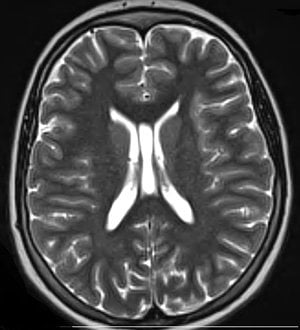

This is an MRI scan of a brain with concussion.

FeaturedNeurology

·October 28, 2013·3 min read

After Concussion, Kids May Need Breaks in School

Researchers recommend accommodations be made in the classroom for children recovering from concussions.

Read More